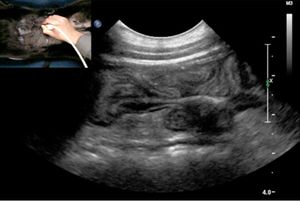

Dr. Ryan King provides a brief overview of which cases are best suited for CT vs. MRI.From the CVC in San Diego, veterinary radiologist Dr. Ryan King provides a brief overview of which cases are best suited for computed tomography (CT) vs. magnetic resonance imaging (MRI).

Dr. Ryan King outlines which forms of imaging are most helpful in certain clinical cases.